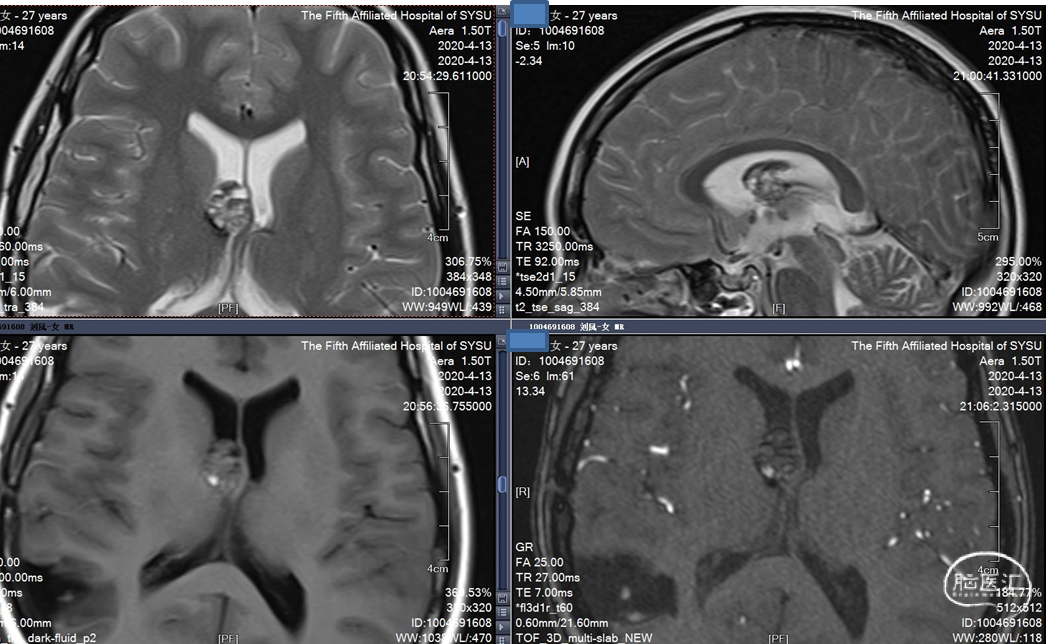

MRI 扫描:有边界,呈圆形。病灶在 T1 加权像呈等信号,在 T2 加权像或注射对比剂后呈高信号,病灶内有混杂低信号,病灶周围有环形低信号带。小型 (<1 cm) 以及非出血性海绵状血管瘤,磁敏感加权成像(SWI)的检出率更高。

患者,女,27岁,发现脑室旁海绵窦状血管瘤,是一种多发的海绵状血管瘤。反复出血两次,用显微镜手术。9天后复查,可见一定血丝,2个月后复查,很干净,病人无明显病灶。今年复查见对侧丘脑有一血肿,手术难度大。